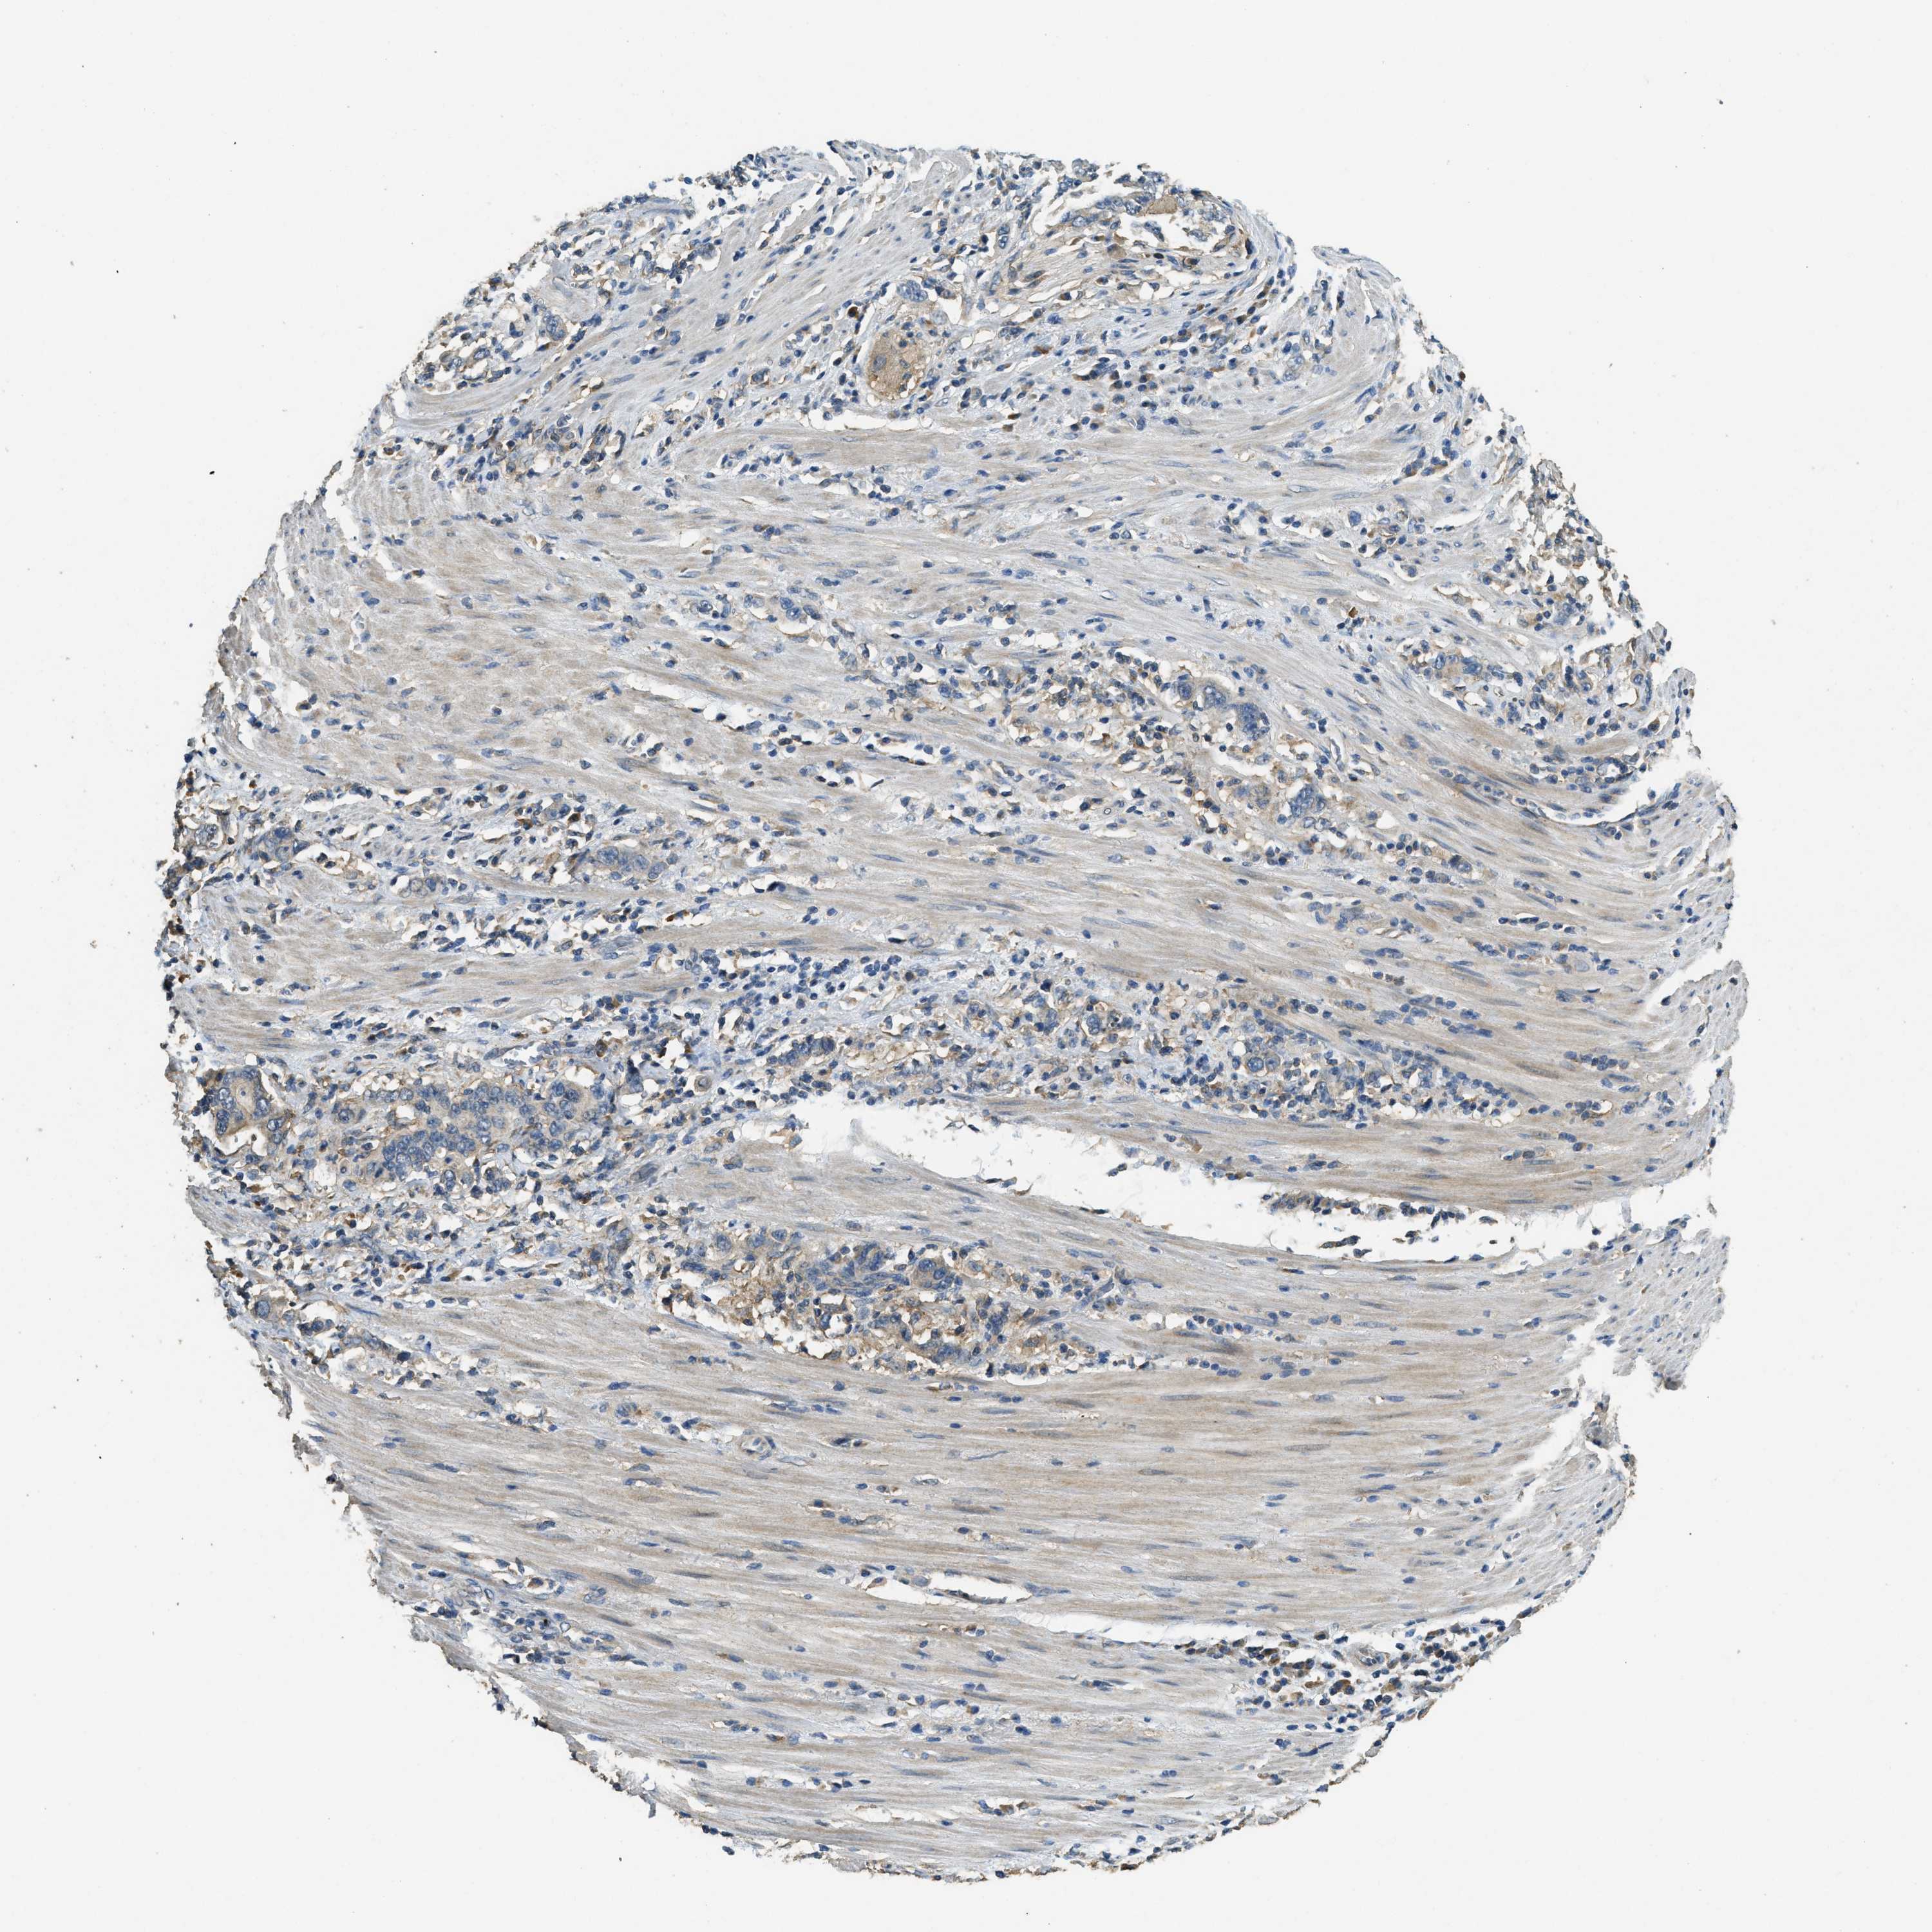

STOMACH CANCER - Protein expressioni

A mouse-over function shows sample information and annotation data. Click on an image to view it in a full screen mode. Samples can be filtered based on level of antibody staining by selecting one or several of the following categories: high, medium, low and not detected. The assay and annotation is described here.

Antibody stainingi

Antibody staining in the annotated cell types in the current human tissue is reported as not detected, low, medium, or high, based on conventional immunohistochemistry profiling in selected tissues. This score is based on the combination of the staining intensity and fraction of stained cells.

Each image is clickable and will lead to virtual microscopy that enables deeper exploration of all samples and also displays staining intensity scores, fraction scores and subcellular localization as well as patient and tissue information for each sample.

Antibody HPA009285

Antibody HPA017139

Antibody CAB017826

Staining

High

Medium

Low

Not detected

Intensity

Strong

Moderate

Weak

Negative

Quantity

>75%

75%-25%

<25%

None

Location

Nuclear

Cytoplasmic/membranous

Cytoplasmic/membranous,nuclear

Adenocarcinoma, NOS

Adenocarcinoma, High grade